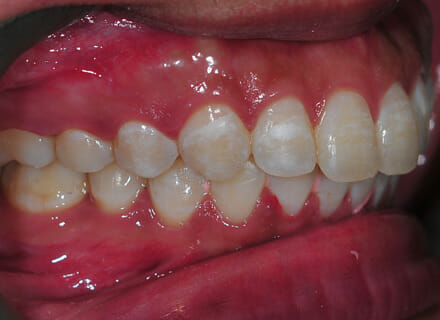

This lady came to us because she said she was goofy – her front teeth were sticking out. In the lower jaw, the teeth didn’t have enough room so 2 teeth had been pushed out of the bite altogether. We fitted a clear brace and were able to reduce the overbite by 80%. We also managed to pull the lower premolars back into the arch. This lady did not require any extractions. She was so pleased with the results especially as no healthy teeth were removed!